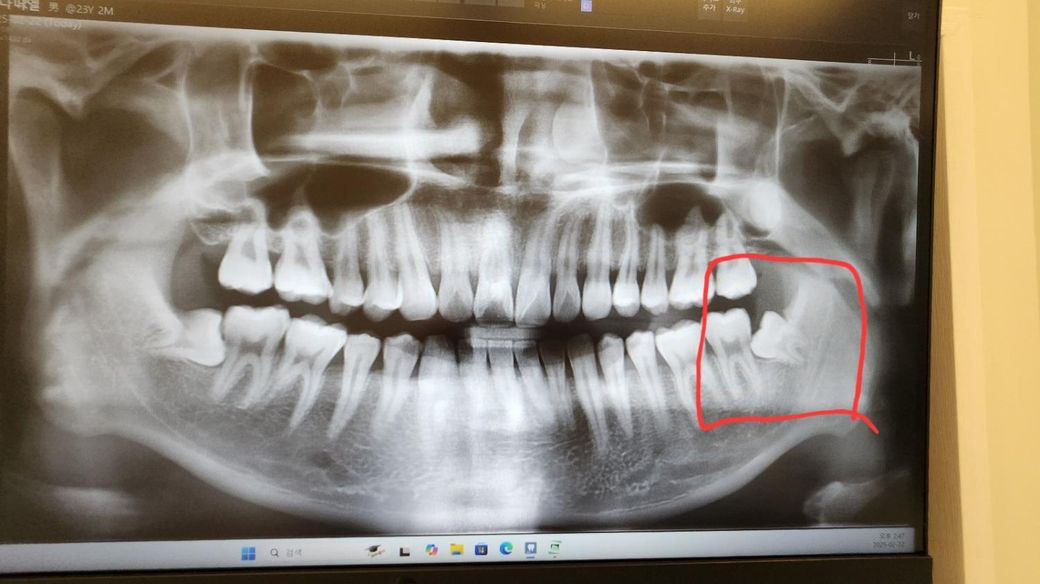

사랑니는 건강보험도 적용되는데 왜 이렇게 저는 비싸게 발치한건지.. 아래 사진 빨간색부분이 뽑았던 사랑니인데.. 이게 15만원 들 정도로 뽑기힘든건가요?